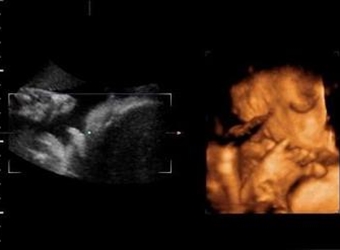

四维彩超是目前比较流行的孕检之一,四维能对胎儿头面部立体成像,可清晰显示胎儿的状态,网上很多四维是女孩但是却生了男孩的案例,那么四维女孩翻盘几率大吗…

四维彩超是实时的立体成像,在孕检的时候主要是帮助筛查胎儿的畸形,四维由于清晰度高也有用来判断胎儿男女,那么四维看是男孩有可能是女孩吗,四维男翻女的几…

四维彩超的报告中有很多的指标,网上也流传了很多通过报告单看男孩女孩的方法,那么四维胎儿双侧肾盂无分离是男是女,5个月四维如何看男女呢?更多关于生男生…

很多网上的宝妈都有看到这个情况,那就是做了四维彩超是男孩,但是却生了女孩,很多宝妈担心四维做的是男宝有可能翻盘吗,为什么四维男宝变女宝?更多关于生男…

网上有一种说法是,在做四维彩超的时候,如果是女宝宝是比较不容易配合的,如果是男宝宝更容易通过,那么是不是四维女宝更容易配合呢,四维女宝特征有哪些?更…

做四维彩超的时候,需要宝宝在肚子里动起来,有配合效果才是最好的,网上说做四维的时候不配合的都是女宝宝,那么这种说法是真的吗,四维是女宝还会翻盘吗?更…

很多宝妈都有在网上看到,做四维彩超的结果是女孩,但是最后生下的是男孩的案例,那么四维看是女孩最后会是男孩吗,女孩翻盘男孩的几率大不大?更多关于生男生…

网上流传着很多宝妈做四维彩超检查,医生说是男孩,但是结果生出来是女孩的案例,那么四维彩超男孩翻盘实例有哪些,为什么四维是男孩结果生女孩?更多关于生男…